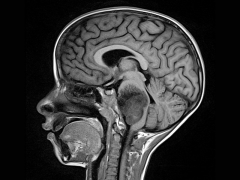

脑干神经胶质瘤是一种发生在脑干的肿瘤。它较常见于20岁以下的...

越来越多的证据表明,儿童高级别胶质瘤表现出与成人患者明显...